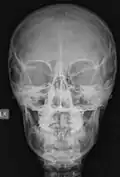

Las imágenes digitales que se adquieren hoy en día, ya sea en radiología digital indirecta (CR) o directa (DR), presentan una gran ventaja debido a la potencialidad que su manejo informático ofrece, en el cual es posible sobre la base de una imagen adquirida aplicar diferentes herramientas como filtros que permiten mejorar el realce de los bordes, suavizar, analizar el histograma y realizar análisis de la calidad de la imagen obtenida. Estas herramientas están disponibles en las consolas de procesado de imágenes de los equipos radiológicos, pero también existen programas dedicados como ImageJ que permiten realizar el análisis de las imágenes, ya sean de uso médico o no. Una de las funcionalidades de ImageJ es la posibilidad de "retocar" la imagen aplicando filtros como los que se observan en las siguientes imágenes en las cuales hemos aplicado a la imagen base de una radiografía de cráneo (al centro) un filtro que permite suavizar la imagen (Imagen 1) y luego a la misma imagen le hemos aplicado un filtro de reforzamiento de los bordes (Imagen 2).